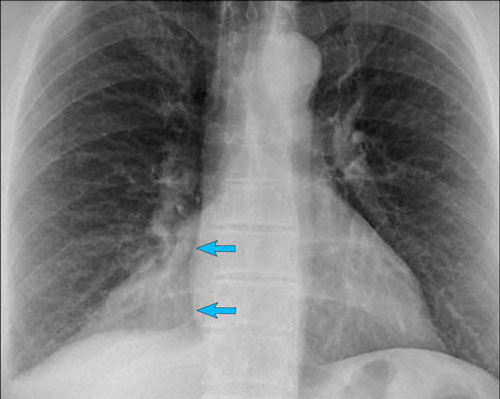

Displacement of the Azygoesophageal Line (2) – Subcarinal Lymphadenopathy

A common cause of displacement of the azygoesophageal line is subcarinal lymphadenopathy (station 7).

On the chest X-ray, note superior displacement of the azygoesophageal line just below the carina, consistent with enlarged subcarinal lymph nodes (black arrow).

Additional right paratracheal lymphadenopathy is seen, displacing the right paratracheal stripe (white arrow) and deviating the trachea to the left.